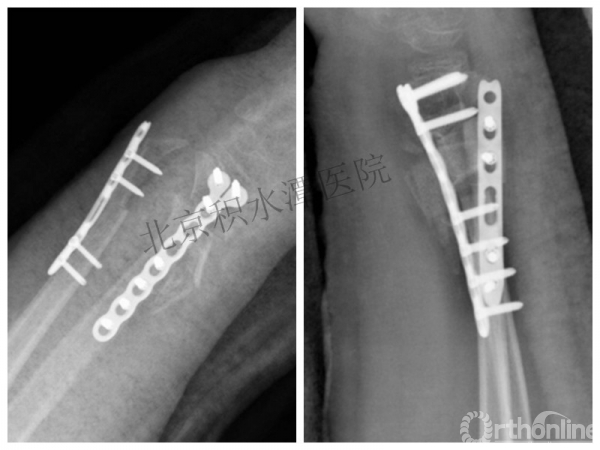

医生的处理方法!——医生终于没有坚持自己的原则!

伤后40天—切开复位内固定!

伤后18个月

如何面对?

心情之压抑无以言表!

手术历时近 5小时!心情之压抑无以言表!因为当时的经治医生是他们的进修生!感觉是他们的失职甚至渎职!

唯一可以肯定—预后不佳!郭教授是党员!是无神论者!但是很诡异的事情:手术中发生—C形臂看不清!拍片条件总是调节不好!手术器械换了三套!内固定钢板总不合适!

术后15月,虽然家长满意了,但是他们医生不满意!